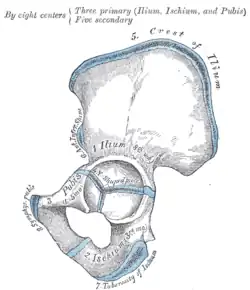

The pelvis, specifically the hip bone, comprises three bones: the ilium, pubis, and ischium. During growth, the junctions between these bones, known as growth plates, remain open. Initially connected by connective tissue, these plates later become flexible through cartilage and ossify only at the end of skeletal growth. The three growth plates converge at the center of the hip joint's acetabulum, forming the Y-suture.[1][2]